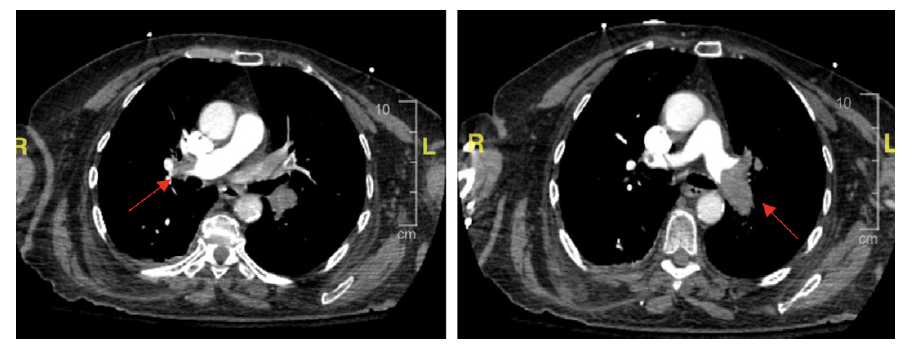

A PE protocol computed tomography angiography revealed inversion of the ventricular ratio with straightening of the interventricular septum compatible with right ventricle strain. Pulmonary emboli extending into the right and left pulmonary arteries with partially occluded filling defects extending into all lobes (Figure 4).